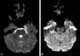

Turbinate enlargement